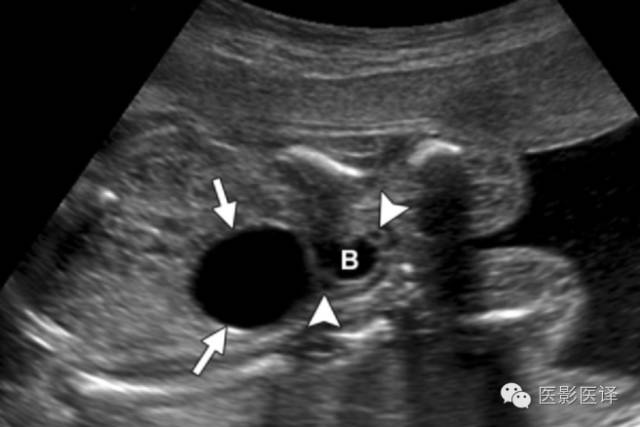

Nussbaum等最早将新生儿卵巢囊肿分为单纯性和复杂性。单纯性卵巢囊肿是圆的、无回声的、单房和薄壁的(图1)。它们更经常为单侧而非双侧、更经常为腹内而非盆腔内。单纯性囊肿内偶尔可见单个分隔(图2)。直径小于20mm的卵巢囊性结构被认为是成熟卵泡,为生理性而非病理性。直径大于20mm的囊肿则考虑为异常。“子囊”征描述的是囊内一个小的、圆形、无回声结构(图3)。既往报道认为这是卵巢囊肿的特征。【在一个23例囊性病变的研究中(包括新生儿、婴儿及儿童),11例发现子囊,占卵巢囊肿的82%(敏感度82%,特异度100%,阳性预测值100%),在其他囊性病变中未发现子囊,包括淋巴管瘤、肠重复畸形、肠囊肿、胎粪假性囊肿、阴道积液和脐尿管囊肿。】

图1:单纯性卵巢囊肿。冠状位胎儿超声图像显示一个边界清楚的薄壁无回声囊肿(箭),高于膀胱(B)位于腹内中线之外。注意脐动脉(箭头)在膀胱两侧。

图3:单纯性卵巢囊肿。(a)矢状位胎儿超声图像显示一个边界清楚薄壁腹内囊肿(箭头),其内可见一个子囊(箭)。囊肿位于膀胱(B)上方腹中线区。Uv=脐静脉。(b)同一病人轴位超声多普勒图像显示在薄壁卵巢囊肿中有两个子囊(箭头)